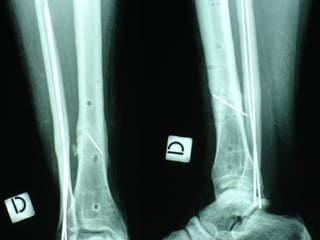

Dal Gennaio 2000 al Febbraio 2006 abbiamo trattato 167 fratture chiuse  con placca percutanea  in 164 pazienti :  27 lesioni diafisarie di gamba, 12 piloni tibiali ,  11 fratture prossimali di tibia, 36 fratture sovracondiloidee di femore, 17 fratture diafisarie di femore, 43 fratture metaepifisarie prossimali di omero, 21 diafisarie d’omero.  156 guarigioni 8 fallimenti

Dal Giugno 2002 al Dicembre 2004 abbiamo trattato 5 fratture esposte: 3 di tibia e 2 di ulna 5 guarigioni

I buoni risultati ottenuti dipendono da 5 punti fondamentali:   una accurata riduzione percutanea della frattura  precise vie di accesso  l’utilizzo della placca che consenta il più lungo braccio di leva possibile il pretensionamento della placca  una sintesi con un ridotto numero di viti